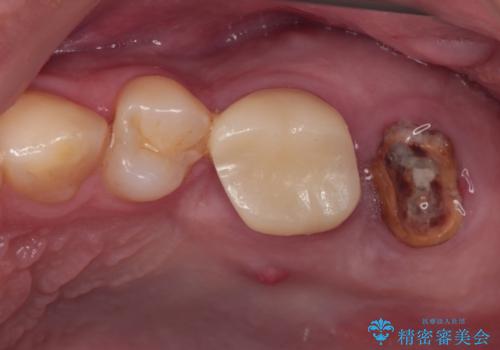

- 以前詰め物をした奥歯に物が頻繁に挟まるとのことで来院された患者様です。

充填物は形態が不正であり、歯肉付近にバリのように充填材料が飛び出していたため、歯肉が腫れやすい状態でした。

精密に治療を行うため、型取りを行った上でセラミックインレーによる修復治療を行うこととしました。